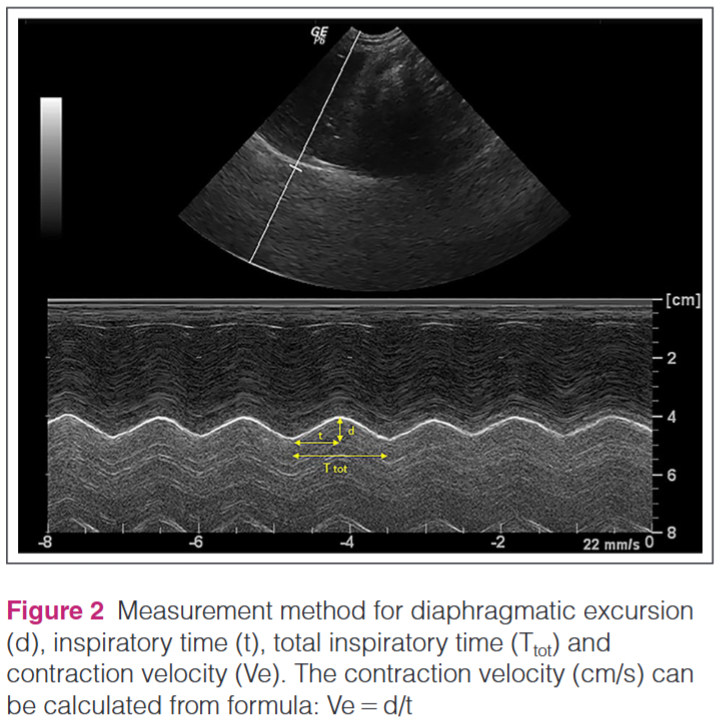

측정의 기준 DE값은 Fig2의 d값에 해당